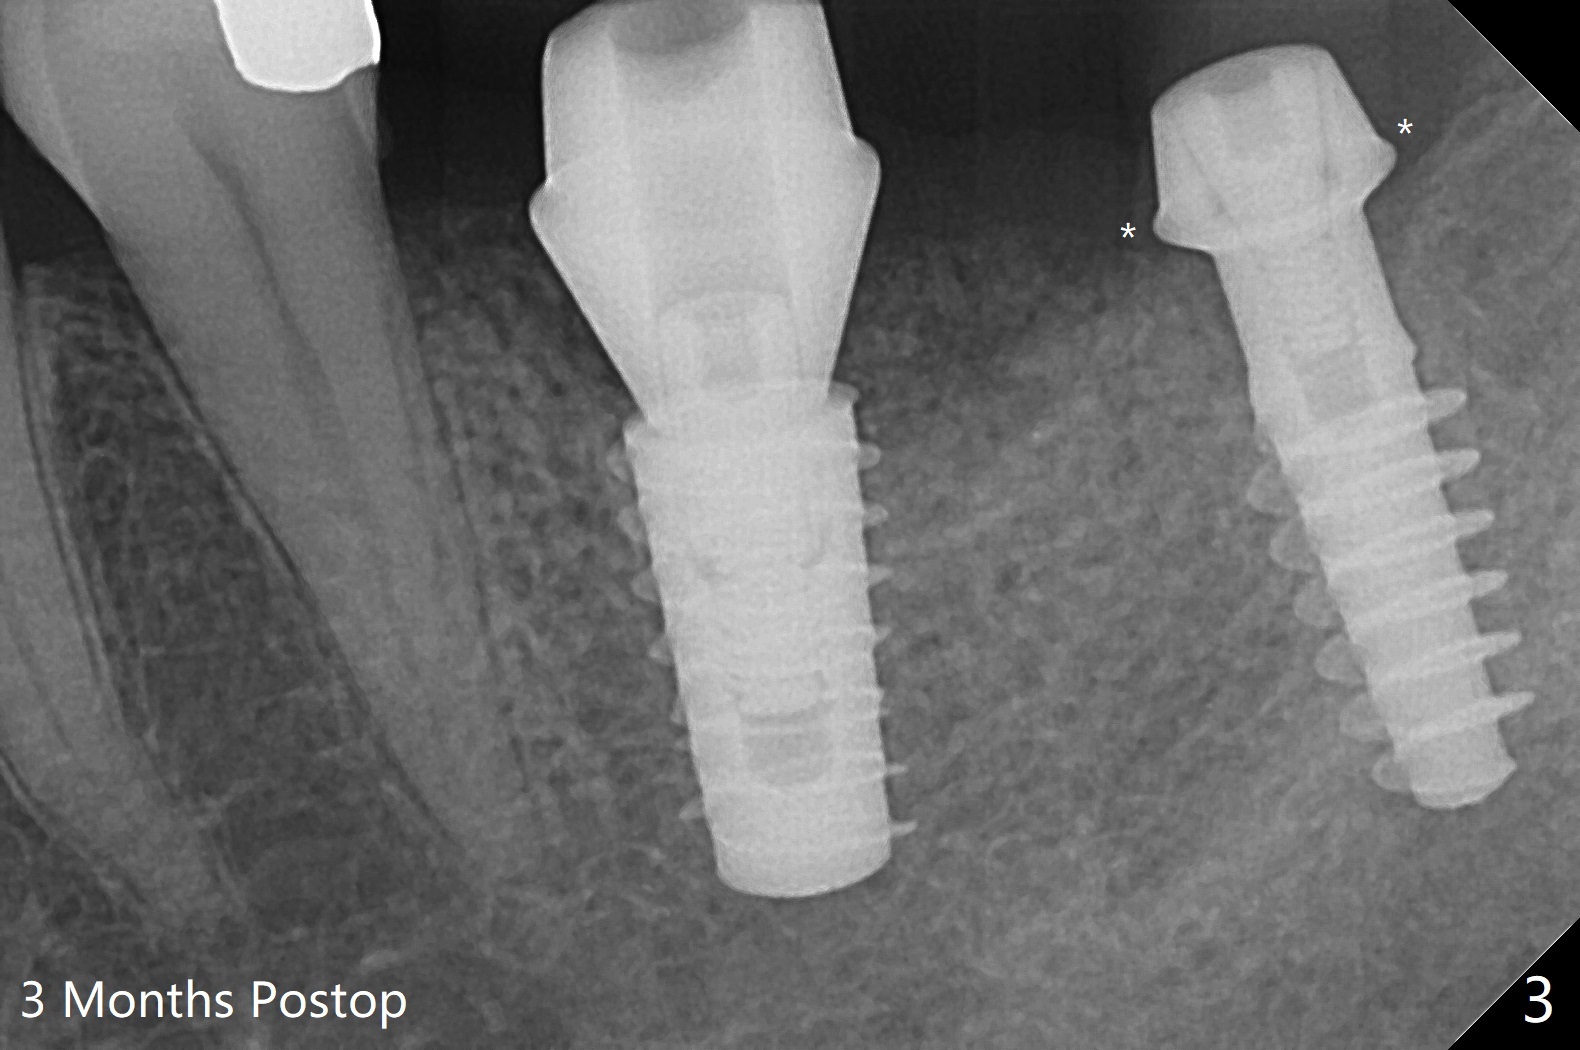

After osteotomy according to drill sequence except no tap at #18, a 5x9 mm FC at #19 achieves insertion torque at 20 Ncm, while a.4.5x9(3) mm Magicore <10 Ncm (Fig.1,2), probably due to the fact the core (middle portion) of Magicore is small, dictating underprep (in diameter) when the bone is not hard. In addition, IS implant driver cannot be engaged to Magicore so that the placement of the latter is free hand. Because of supraeruption of the opposing teeth, the abutment at #19 is heavily reduced, whereas the Magicore is placed super low (Fig.2). The latter may be backed up or crown lengthening is necessary. In fact neither is necessary, since there is crestal bone loss at #18 nearly 3 months postop (Fig.3 *). There is no difficulty in placing 4.5 mm healing cuff.